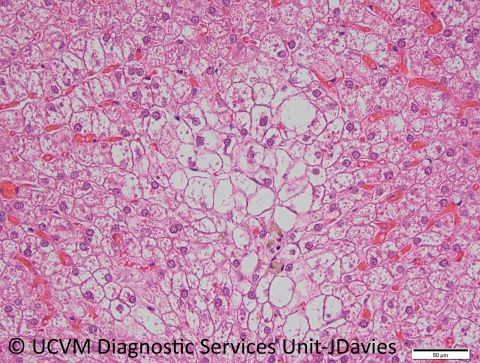

Species: Dog

Specimen: Liver

Shown: Steroid hepatopathy with iatrogenic hyperadrenocorticism